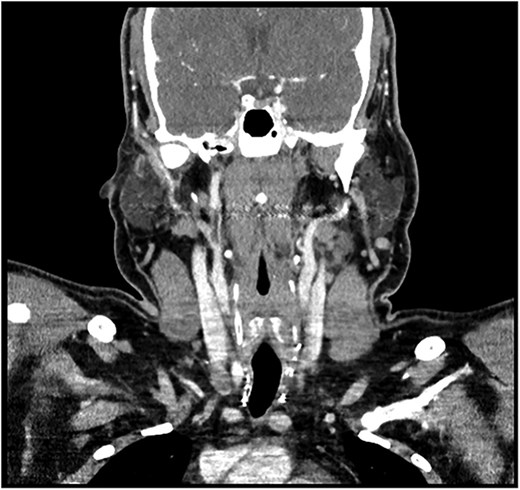

A 28-year-old man with a BMI of 44.3 kg/m2 and, a history of hypertriglyceridemia on gemfibrozil 600 mg complained of neck swelling for 2 years. It began as a nodular swelling at the right supraclavicular region and later spread to the right axillary and left supraclavicular areas. For one month, the patient had an unintentional weight loss of 4 kg and a few episodes of night sweats but no fatigue, fever, or compressive symptoms. He never received any radiation treatment. The family history was positive for an aunt with a malignant thyroid disease, for which she had a total thyroidectomy done. He was also on calcium carbonate 1200 mg orally thrice daily and levothyroxine 200 mcg orally once daily. On general examination, the patient did not look dehydrated, the patient was afebrile and did not appear to be in acute respiratory distress. There was a firm, nontender, nonmobile mass in the right anterior neck which represents lower cervical lymphadenopathy. No thyroid nodules, thrills, or shift of the trachea to the right were found. Abdominal examination was normal, that is, no enlargement or tender masses were felt on abdominal palpation. It started in January 2018 with right sided lymph node enlargement and a detailed assessment was done at a hospital in the United Kingdom (UK) in March 2020. FNA of the neck nodes showed features of HL and the thyroid US showed a hypoechoic nodule with punctate calcifications measuring 3.9 × 1.9 cm and TI-RADS 5. Other findings were bilateral clinically suspicious cervical lymphadenopathy; the largest nodes being 3.6 × 2 cm on the right side and 2.8 × 1.3 cm on the left side. The laboratory findings included T3 of 5.19 pmol/L, T4 of 25 pmol/L, and thyroid stimulating hormone (TSH) of 0.817μIU/ml. According to these observations, the patient underwent further investigations and imaging, CT of the chest revealed necrotic mediastinal, bilateral axillary, and subpectoral lymph nodes suggesting intrathoracic metastases most probably from PTC or lymphoma (Fig. 1). A nuclear medicine scan confirmed FDG-avid disease in the thyroid and nodal areas above the diaphragm. A subsequent FNA of the thyroid nodule revealed papillary thyroid carcinoma (Fig. 2). The patient had a total thyroidectomy, central compartment lymph node dissection, and excision in March 2020. Surgical pathology showed PTC in the right thyroid lobe measuring 2.5 cm in diameter and ipsilateral cervical lymph node involvement. The postoperative treatment included radioactive iodine ablation of 120 mCi in December 2020, and thyroglobulin level was negative. However, the patient got other symptoms by November 2023 after the above-mentioned interventions were conducted. Postoperative US of the neck, done after thyroidectomy, did not demonstrate any thyroid tissue but multiple enlarged cervical lymph nodes, including one that was 2.3 × 1.2 cm in size, with some of the nodes matted and non-encapsulated with loss of fatty hilum. CT imaging revealed an interval increase in the size of right cervical and supraclavicular LN (Fig. 3) and nuclear imaging showed relapsed HL with FDG-avid lymph nodes, above and below the diaphragm. The histopathological examination of the right cervical lymph node excisional biopsy was done and immunohistochemistry staining of markers compatible with CHL was observed (Figs 4 and 5). The tumor cells were positive for CD 30, CD 15 (partially), MUM 1, and PAX 5 (faintly), and the reactive lymphocytes for CD 3 only. The diagnosis of relapse of classical Hodgkin lymphoma (CHL) called for additional oncologic assessment and intervention.

Post-total thyroidectomy and bilateral neck dissection with no signs of recurrence or residual at the thyroid bed. There is a right level IV 11 mm lymph node near the clip of neck dissection.